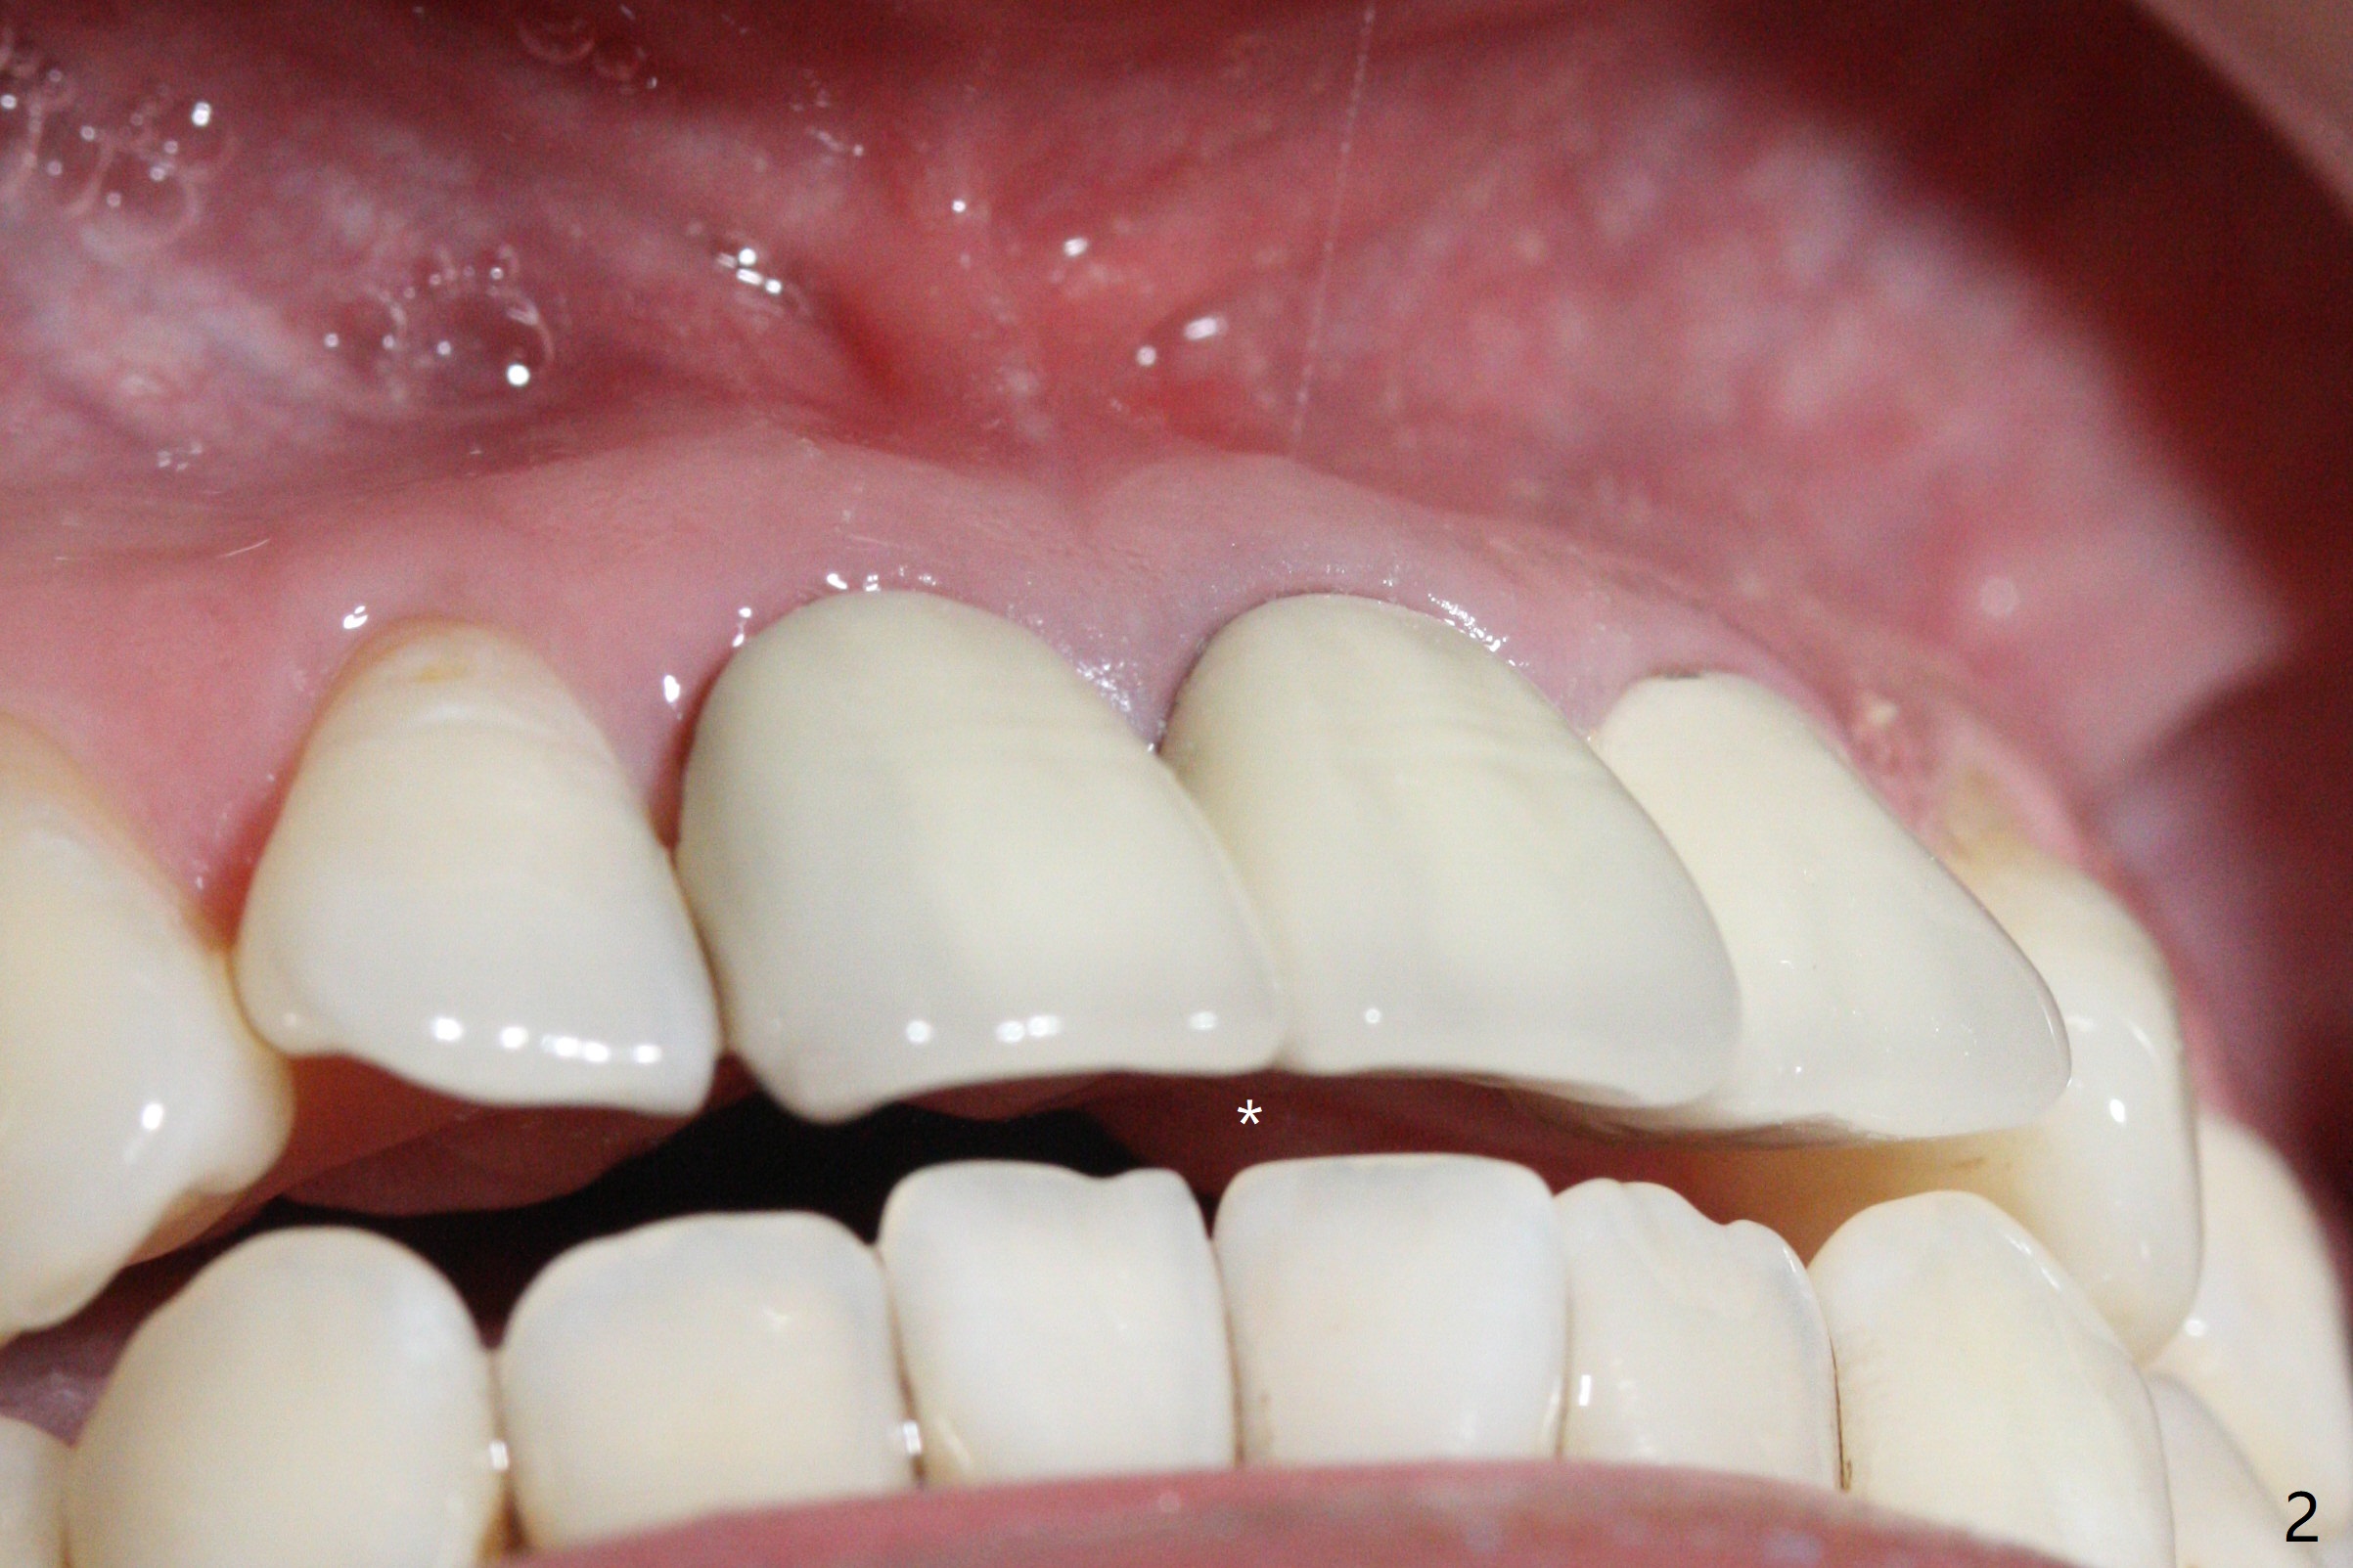

After sectioning the splinted crowns at #8 and 9 (Fig.1,2 (*: open bite)), the tooth #9 is deemed nonsalvageable because of caries and the crown/retainer of #8 is recemented. The trajectory of initial osteotomy is off (Fig.3 (red line: ideal trajectory)). Using Lindamann bur twice does not improve the trajectory (Fig.4,5). It appears that a new osteotomy should be established in the distal wall of the socket (Fig.5 red line (initial entry point and angle), Fig.6). Following sequential osteotomy, a 4x10 mm dummy implant is placed with stability and ~ 3.5 mm apical space (Fig.7 red line). A final implant (4x11.5 mm) is placed subcrestal (except buccal, Fig.8). With further placement of the implant, a 4.5x5.5(3) mm abutment and Vera graft are placed (Fig.9) prior to fabrication of an immediate provisional. In all, a new osteotomy site should be set up when the trajectory is to be changed substantially. There is no gross bone loss 4.5 months postop (Fig.10). There is shade mismatch when a porcelain-fused-Zirconia crown is tried in (Fig.11, as compared to Fig.1). The latter is corrected when a PFM crown is cemented (Fig.12).